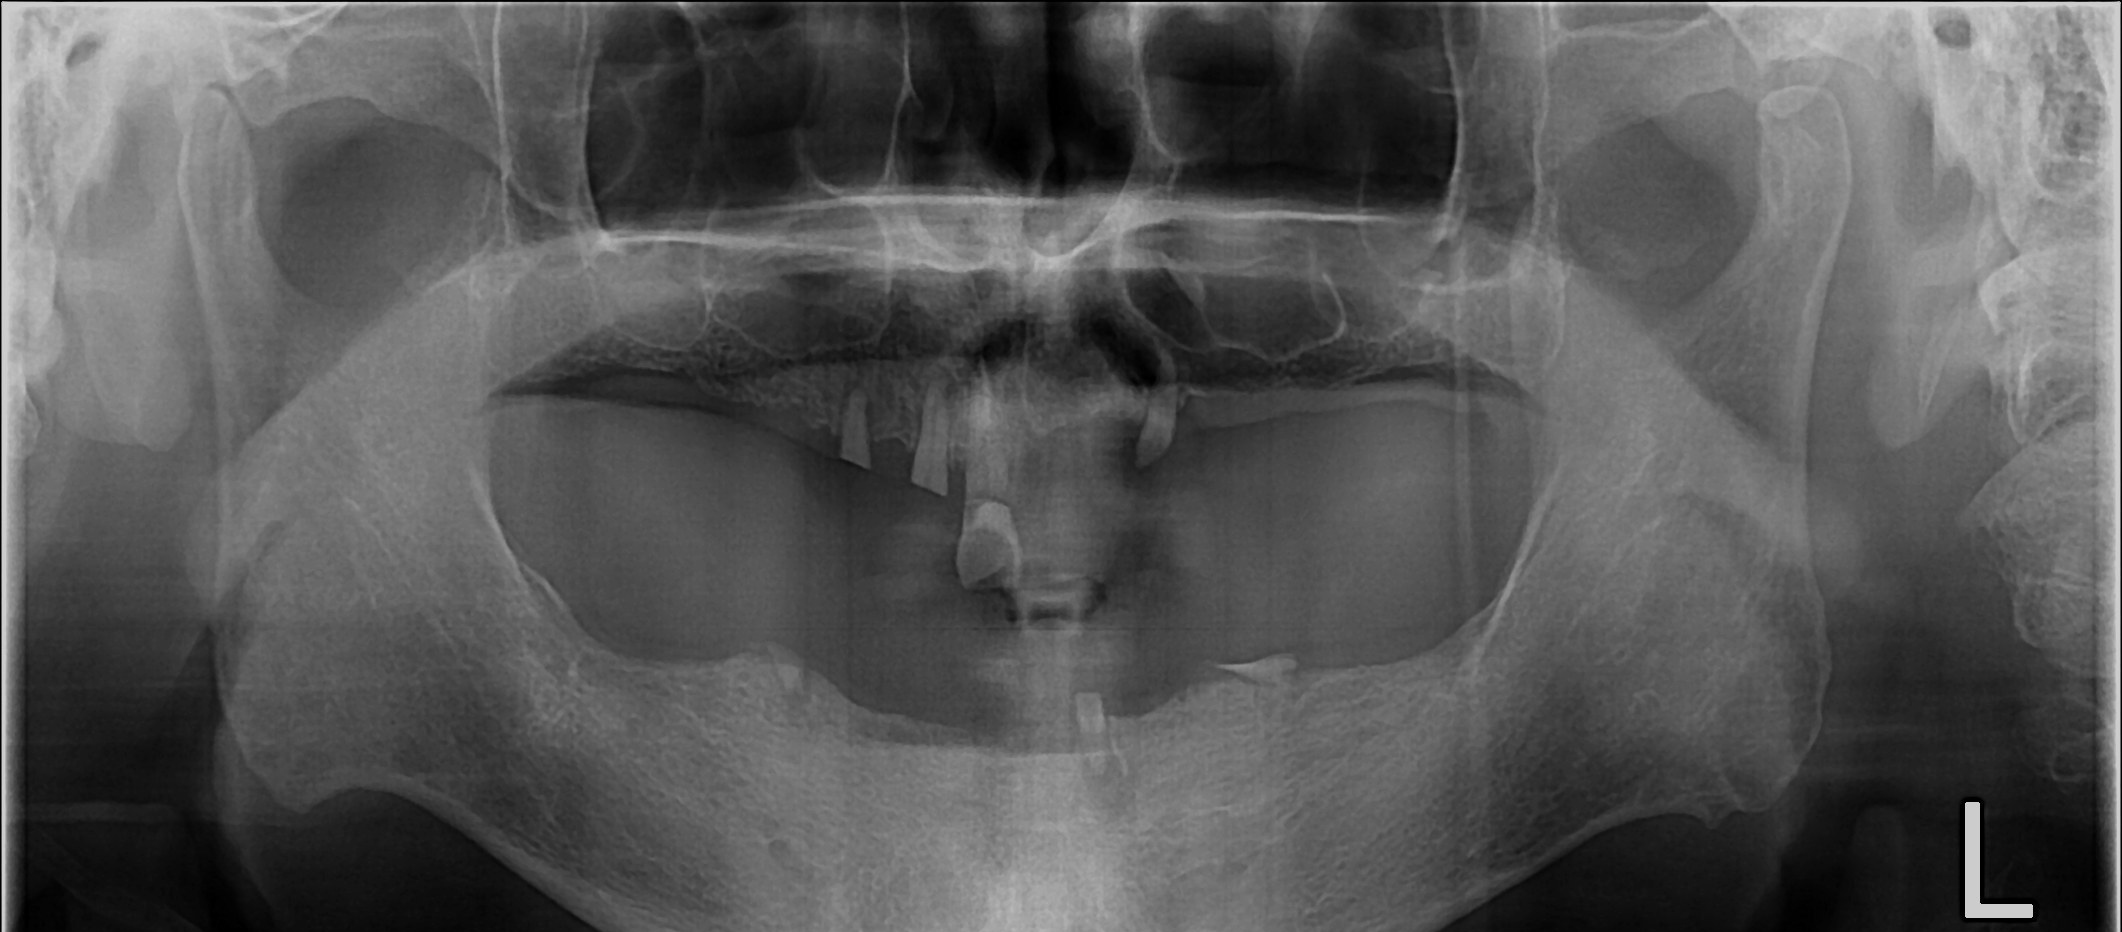

무치악 임플란트 회복

중간과정 ▼

무치악 임플란트 회복 Full Mouth Rehabilitation